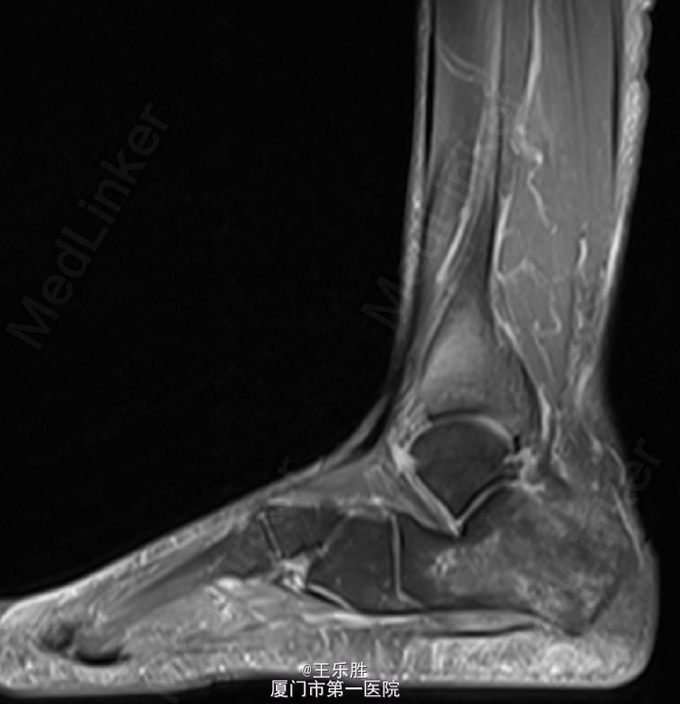

左足跟轻度肿胀,局部皮肤无红肿及皮温升高,轻压痛,左足背动脉搏动存在,肢端血运感觉正常,足趾活动尚可。MRI提示:“左足跟骨水肿”.

初步诊断:左足跟痛. 行CT(左下肢)检查提示:左跟骨骨折,断端稍嵌插、骨质增生样密度增高,跟骨结节骨质增生。余骨未见明显骨质异常,关节间隙如常.

患者属陈旧性骨折,嘱患者避免负重。